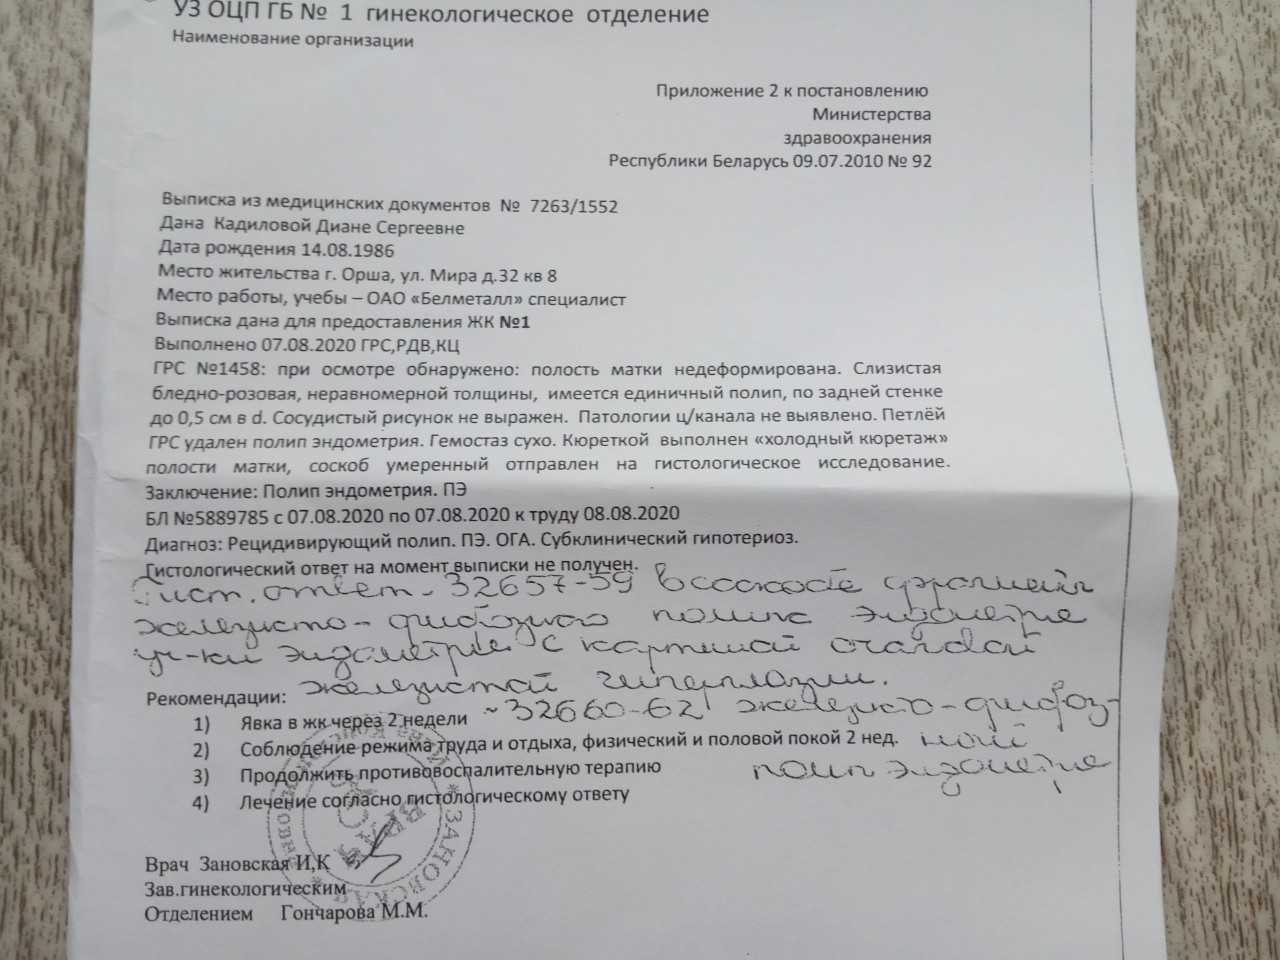

Медицинская диагностика: Гиперплазия эндометрия на УЗИ

Раздел: Мудрость в объективе